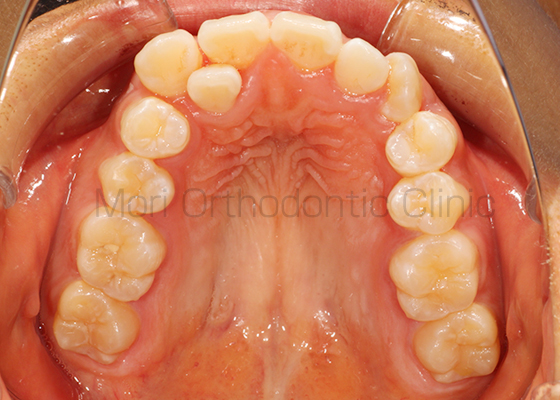

術前

術後

| 主訴 | 歯並び、八重歯 |

|---|---|

| 診断名 | AngleⅡ級叢生 |

| 年齢 | 30歳2か月 |

| 治療装置 | Multi-Bracket(表側矯正)、CARRIERE DISTALIZER |

| 抜歯部位 | 14,24,35,45 |

| 治療期間 | 2年1か月 |

| 治療費 | 825,120円(税込) |

| リスク・副作用 | 矯正治療による歯の移動に伴う痛み、歯根吸収、歯肉退縮、虫歯 |